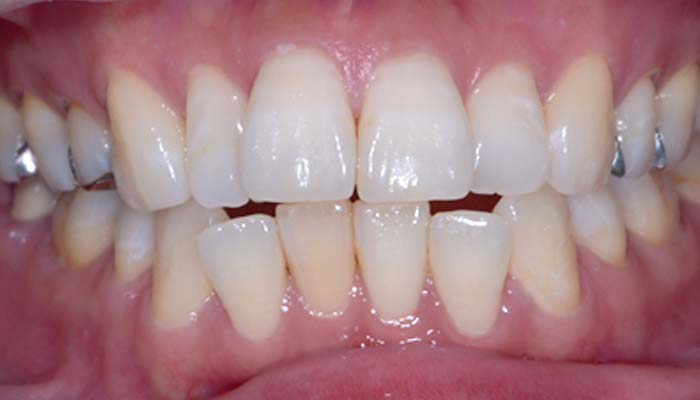

症例1. 上顎のみ部分矯正/

すきっぱ (正中離開)

治療前

治療後

治療期間 | 3ヶ月 |

治療費 | 10万+tax (別途調整料) |